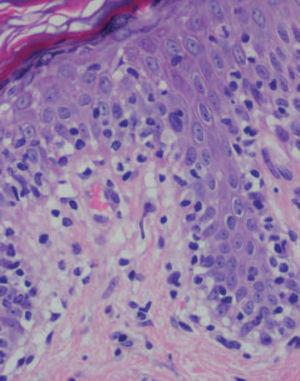

Se practicaron varias biopsias cutáneas, algunas de ellas sin alteraciones significativas. En otras se observó (figs. 4-6) una epidermis con hiperqueratosis y paraqueratosis focal, elongación de las crestas interpapilares y focos de degeneración hidrópica basal, con algún cuerpo apoptótico aislado. En dermis superficial y media existía un infiltrado linfocitario perivascular. Llamaba la atención la exocitosis de linfocitos atípicos intraepidérmicos, alguno de ellos con halo claro perinuclear y en alguna zona incluso iniciando la formación de microabscesos de Pautrier.

Fig. 5.—Exocitosis intraepidérmica de linfocitos atípicos. (Hematoxi-lina-eosina, ×100.)

Como ocurrió con nuestro paciente, el estudio histopatológico en los estadios iniciales de la enfermedad puede ser muy inespecífico, lo que motiva además el retraso diagnóstico. En las fases más avanzadas revela la presencia de epidermotropismo de linfocitos anómalos, que a veces constituyen microabscesos de 5,6,8,11-23. En contraste con la micosis fungoide clásica, en esta variante parece que se observa un epidermotropismo más llamativo en contraste con un infiltrado linfocitario moderado en la dermis24.